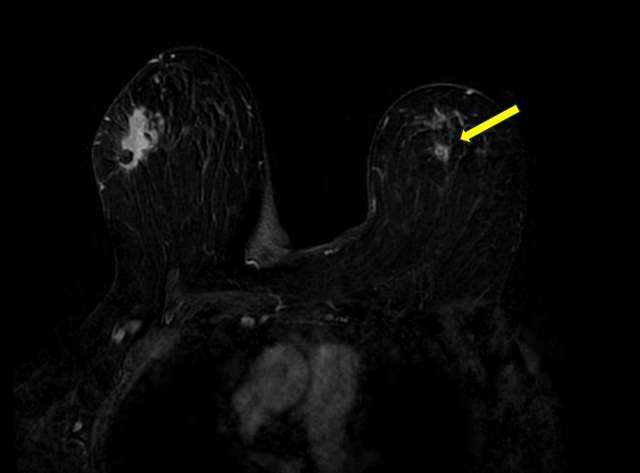

Case: Atypical Lobular Hyperplasia Figure 2

Irregular enhancing mass in the left superior breast (yellow arrow), consistent with biopsy proven atypical lobular hyperplasia. Also noted is invasive ductal carcinoma in the right breast, containing a biopsy marker.